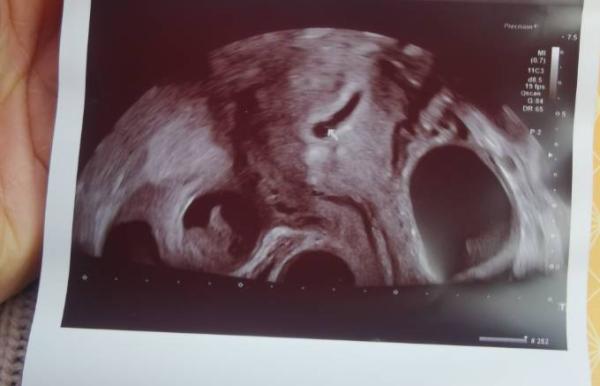

Hatte heute den ersten Ultraschall,, bin heute 5+6 und man sieht die Fruchthöhle und den Dottersack. Und die Eierstöcke sind noch relativ groß von der Stimulation.

Fruchthöhle sagte sie Ärztin ist relativ groß. Wie sah es denn bei euch an 5+6 aus?